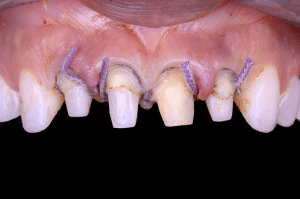

Fig 2.

Avant de procéder au scellement des éléments provisoires, des brins de fils interdentaire sont noués autour de chaque embrasure, par un nœud simple.